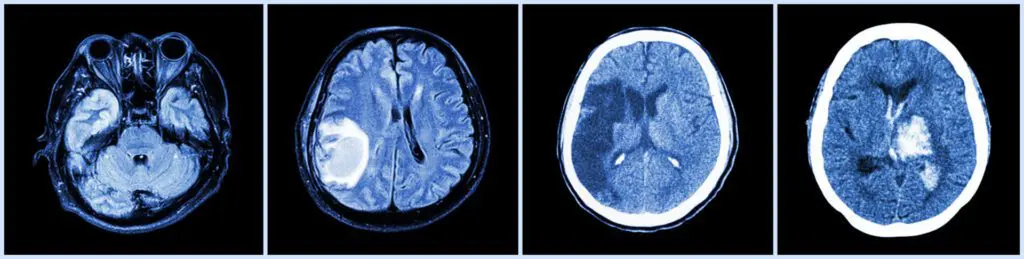

Imaging (MRI or CT Scan): Imaging tests are crucial for identifying any structural abnormalities, such as tumors or aneurysms, that may be compressing the cranial nerves.